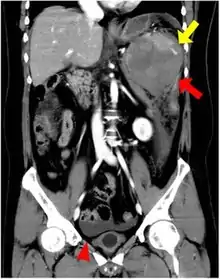

CT scan of an accessory spleen (circular object in center of image) between the spleen and left kidney.

An accessory spleen is a small nodule of splenic tissue found apart from the main body of the spleen. Accessory spleens are found in approximately 10 percent of the population[1] and are typically around 1 centimetre in diameter. They may resemble a lymph node or a small spleen. They form either by the result of developmental anomalies or trauma.[2] They are medically significant in that they may result in interpretation errors in diagnostic imaging[2] or continued symptoms after therapeutic splenectomy.[1] Polysplenia is the presence of multiple accessory spleens rather than one normal spleen.

If splenectomy is performed for conditions in which blood cells are sequestered in the spleen, failure to remove accessory spleens may result in the failure of the condition to resolve.[1] During medical imaging, accessory spleens may be confused for enlarged lymph nodes or neoplastic growth in the tail of the pancreas,[5] gastrointestinal tract, adrenal glands or gonads.[2]